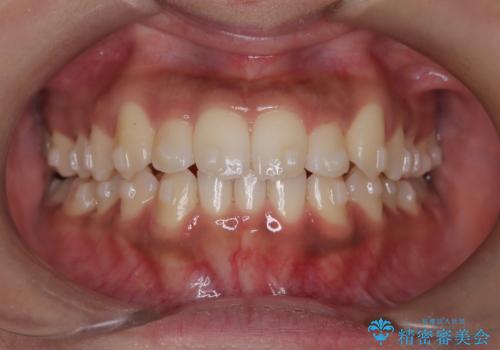

【インビザライン】笑ったときに目立つ八重歯をなおしたい

- 笑ったときに八重歯が見えることを主訴に来院されました。

下の前歯が一本足りない患者様でしたので、シミュレーションを作り、事前に患者様と治療ゴールのイメージをしっかり共有したうえでインビザラインを用いて治療を行っています。

奥歯を後ろのほうに動かすことで、前歯も少し下がることができ、矯正後の口元も満足していただきました。